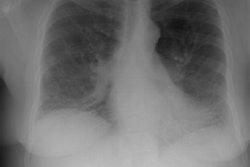

OBJECTIVE. We reviewed the imaging findings in nine patients with idiopathic giant bullous emphysema. This progressive condition is characterized by large bullae, usually seen in association with several forms of emphysema, and usually occurs in young men, most of whom are smokers. MATERIALS AND METHODS. Nine patients with chest radiographic evidence of a bulla or bullae occupying at least one third of a hemithorax, who had also been examined with high-resolution CT, were included in this retrospective study. We examined the size, distribution, and locations of bullae. On high-resolution CT scans, bullae were categorized as predominantly subpleural or intraparenchymal. RESULTS. In eight of the nine cases, the chest radiographs showed variable asymmetry in the distribution of bullae. Bullous disease involved predominantly the upper lobes. High-resolution CT showed bullae from 1 to 20 cm in diameter, but most were 2-8 cm in diameter. Paraseptal emphysema and subpleural bullae were the predominant findings in all nine patients. Seven patients had separate centrilobular emphysema of various degrees and intraparenchymal bullae. None of the intraparenchymal bullae were larger than 2-3 cm. Additionally, two non-small-cell lung cancers were seen in our series. CONCLUSION. The dominant and consistent feature seen on high-resolution CT scans in both smokers and nonsmokers is extensive paraseptal emphysema merging into giant bullae. Associated centrilobular emphysema, seen in cigarette smokers, is the important variable finding for determining the extent of underlying parenchymal disease, which may help in the preoperative assessment of giant bullous lung disease.